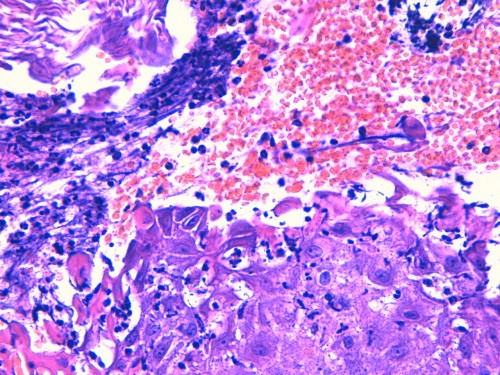

@ Biopsies (LAPVSO) : « Quatre biopsies cutanées sont examinées selon différents niveaux de section et après réaction au PAS.

L’épiderme apparaît multifocalement creusé de vésiculo-pustules relativement étendues. Elles peuvent se développer sous la couche cornée ou dans la couche granuleuse ou ponter plusieurs abouchements folliculaires contigus. Les squamo-croûtes ou les vésiculo-pustules contiennent des cellules épithéliales acidophiles, acantholysées, mêlées à des granulocytes neutrophiles ou éosinophiles et à des lamelles de kératine. Sur le plancher des vésiculo-pustules, constitué de l’épiderme et des infundibula folliculaires, on observe nettement un détachement, par plages, d’acanthocytes qui s’arrondissent, deviennent acidophiles, bombés, présentant encore un noyau viable. Le siège de ces pustules acantholytiques réside le plus souvent dans la couche granuleuse de l’épiderme ou au dessus dans la couche cornée. Le derme sous-jacent est paradoxalement peu inflammatoire. On y observe un infiltrat périvasculaire à diffus, exsudatif, relativement riche en cellules mastocytaires et en granulocytes éosinophiles, accompagnés de quelques lymphocytes. »

Photo 16 : histologie, détachement de cellules acantholytiques acidophiles du plancher de la pustule

Aspect histologique d’une pustulose sous cornée granulocytaire acantholytique amicrobienne sans détection d’éléments figurés pathogènes ni parasitaires ni fongiques.

Aspect histologique orientant vers un pemphigus superficiel auto-immun ou éventuellement une éruption médicamenteuse mimant un pemphigus superficiel.